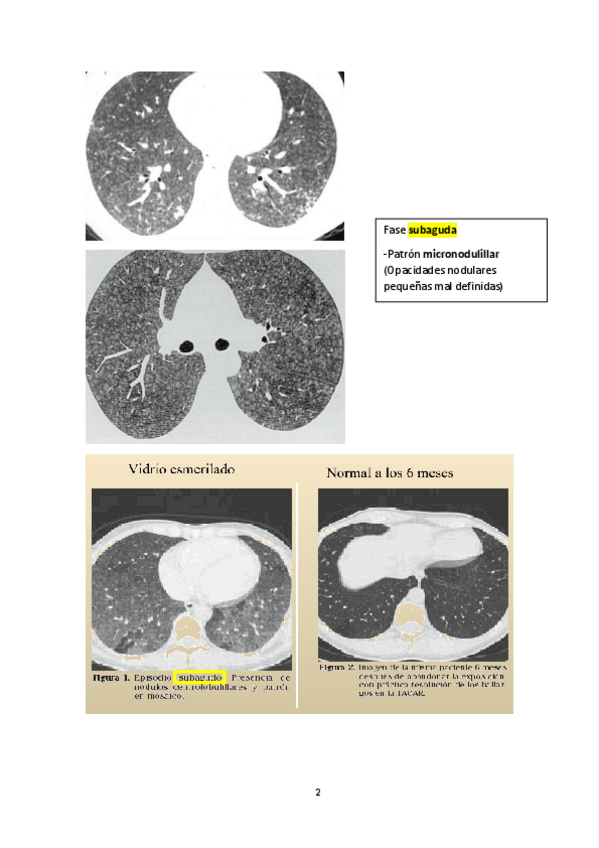

He publicado nuevos apuntes de 4º Enfermedades del Aparato Respiratorio: NEUMONITIS.pdf

5 páginas

He publicado nuevos apuntes de 4º Enfermedades del Aparato Respiratorio: Respiratorio-Anexo-T11.pdf